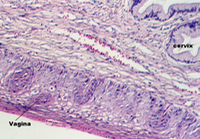

At about day 15, the trophoblast shell sends villi deeper into the endometrium. These villi are filled with mesenchyme (called secondary villi) and will, by the end of the 3rd week, contain blood vessels (tertiary villi.) Maternal blood percolates slowly in the space created outside the villus. Look at slide 89 in your class slide set. The right hand section shows a young placenta. Look at the section with the low power. In the lower left of the section, there is a twisted, folded and otherwise distorted portion of the chorionic plate. It is amass of connective tissue covered by two types of epithelia. The side lined by flat epithelium is continuous with the amniotic sac. It faces the embryo. The side lined by two layers of trophoblast cells faces the uterus and gives rise to the villi. The photos below show the chorionic plate and related structures. The first photo shows the side facing the uterus.

The following photos show the portion facing the embryo. It is distinguished by the simple squamous epithelium. In the lower right corner, one can see the denser epithelium of the side facing the uterus.